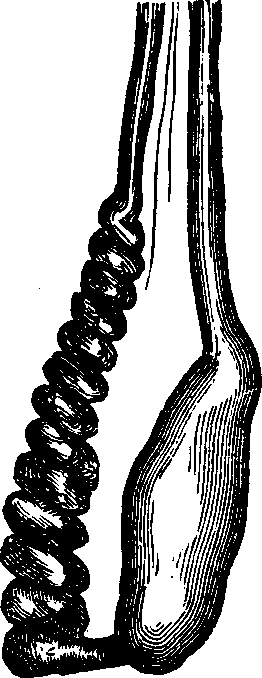

Elongation of the Neck of the Womb. An elongated condition of the neck of the womb, illustrated by Fig. 9, is frequently a cause of sterility. If this part is elongated, slim and pointed, as shown in the illustration, it is apt to curve or bend upon itself, thus constricting the passage through it and preventing the transit of seminal fluid into the womb. An eminent author says, "Even a slight degree of elongation, in which the cervix, or neck, has a conical shape, has been observed to be frequently followed by that condition [sterility]." Our own observations, embracing the examination of hundreds of sterile women annually, lead us to believe that this condition is among the common causes of barrenness. But, fortunately, it is one of those most easily overcome.

Treatment. If the neck is only slightly elongated, this consists in dividing the slim projecting part, by the use of the hysterotome, If it be a more aggravated case, a portion of the womb must be removed. This operation is perfectly safe and simple, and, strange as it may seem to those who are not familiar with operations upon the womb, is not painful. We have never seen any bad results follow it, but have known it to be the means of rendering numerous barren women fruitful.